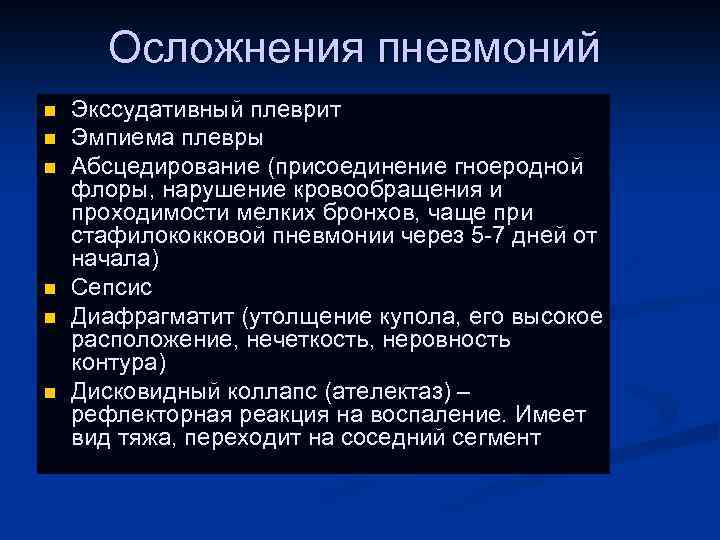

Осложнения пневмоний n n n Экссудативный плеврит Эмпиема плевры Абсцедирование (присоединение гноеродной флоры, нарушение кровообращения и проходимости мелких бронхов, чаще при стафилококковой пневмонии через 5 -7 дней от начала) Сепсис Диафрагматит (утолщение купола, его высокое расположение, нечеткость, неровность контура) Дисковидный коллапс (ателектаз) – рефлекторная реакция на воспаление. Имеет вид тяжа, переходит на соседний сегмент